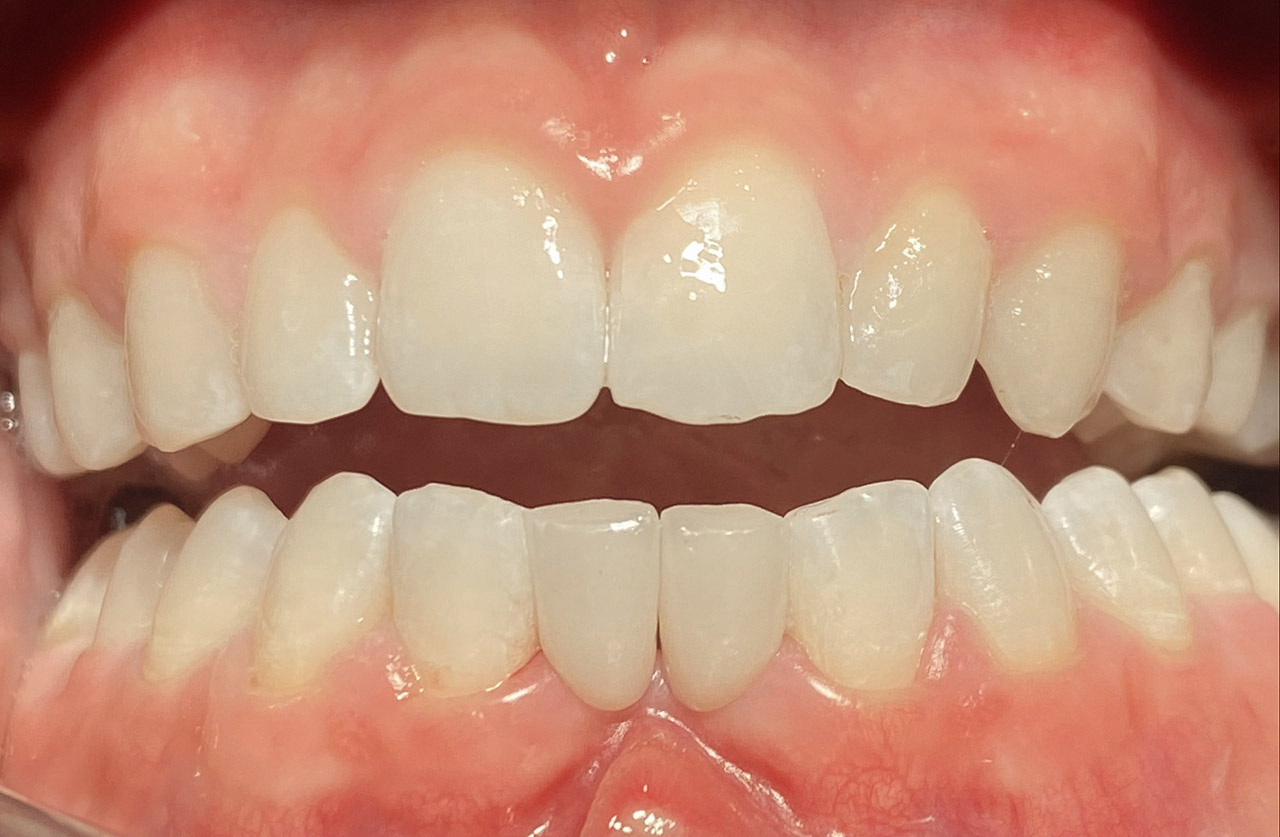

Aplasien/Nichtanlagen, dadurch bleibende Milchzähne, Diasteme/Zahnlücken,

Bleaching/Bleichen, Positionierung der Zähne/Kieferorthopädie (Dr. Maija Eltz), Verblendung mit Veneers/Keramikschalen.